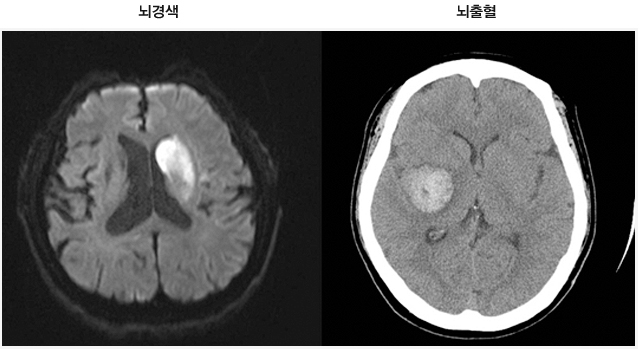

먼저, 뇌경색이 무엇인지에 대해 간단히 설명드리겠습니다. 뇌경색은 뇌에 공급되는 혈액이 차단되어 뇌세포가 손상되는 상태를 의미합니다. 대개 두 가지 종류가 있으며, 하나는 혈전으로 인한 허혈 뇌경색이고, 다른 하나는 출혈로 인한 뇌출혈입니다. 이 두 가지 모두 뇌에 큰 영향을 미치며, 생명을 위협할 수 있는 심각한 질환입니다.